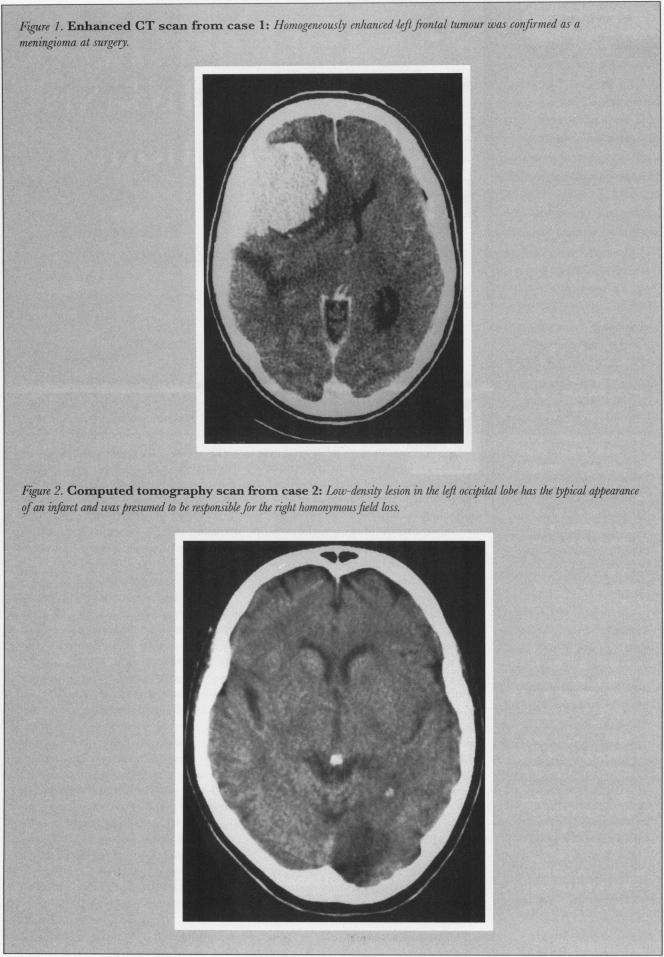

脑肿瘤患者的癫痫预防。家庭医生简要综述与指南。

Seizure prophylaxis for brain tumour patients. Brief review and guide for family physicians.

Brain tumours are relatively uncommon, but family physicians are sometimes confronted with the somewhat unnerving task of carrying on the day-to-day management of these patients. The authors examine some of the problems encountered in preventing seizures among brain tumour patients. Using illustrative clinical cases and a review of the relevant literature, guidelines are provided for the institution, maintenance, and in some cases discontinuation of seizure prophylaxis for this group of patients.

摘要